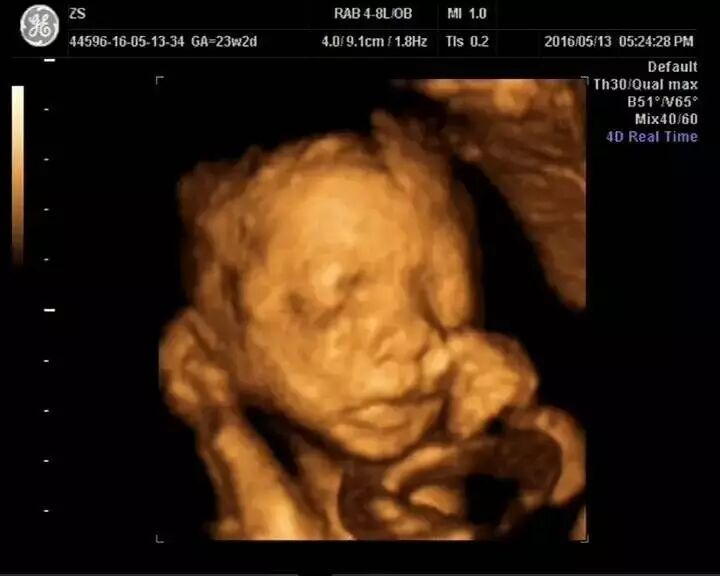

如今,老二在肚子里即将出世,辰辰妈整个生活完全幸福得像花儿一样~~

说起自己未来的二孩生活,辰辰妈充满了信心,如今每天最幸福的事就是女儿和爸爸一起捧着妈妈的肚子亲吻,一起听肚子里的声音。亲爱的小宝贝,你感觉到了吗?爸爸、妈妈和姐姐,都等着你的降临~~~~